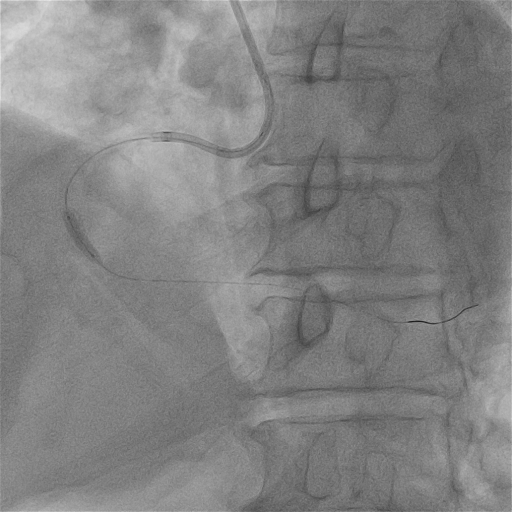

ROTA 1.5Burr再次旋磨远段

再次送入1.5mm旋磨头对远端病变进行旋磨,顺利通过病变处并进行充分打磨。

球囊扩张

2.0mm高压球囊充分扩张远端病变;造影示RCA远端病变处扩张效果良好,近、中段病变扩张不充分。